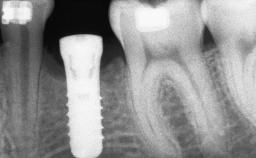

A woman in her mid-fifties was referred by a dental student for dental implant placement. Both posterior segments of the mandible had been edentulous for more than 4 years, the only residual tooth being the right lower first premolar. The patient had used a removable partial denture but was not entirely satisfied with its function. The clinical examination revealed a sharp edentulous ridge in both posterior segments of the mandible, and the patient was told that it would not be possible to insert implants into this thin edentulous ridge without significant augmentation of the alveolar ridge. Her medical history revealed no significant findings and no underlying disease that might have complicated surgical procedures. During the presurgical examination, the patient reported that she was a little apprehensive about bone grafting. After being informed about the surgical procedures and potential postoperative complications, she accepted the proposed surgical plan of bone grafting and subsequent placement of implants.

| Bone Volume | Deficient horizontally, requiring prior grafting |